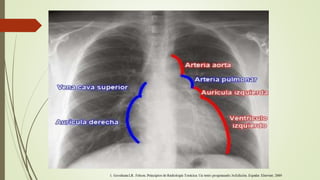

MEDIASTINO

• Es el espacio situado entre las pleuras parietales mediales, que

contiene las estructuras centrales cardiovasculares,

traqueobronquiales y el esófago, rodeados por grasa, en cuyo

seno hay ganglios linfáticos.

• Se divide en compartimentos y la clasificación más utilizada es

la anatomoradiológica, en la cual una línea trazada desde el

angulo esternal por delante hasta el cuarto espacio

intervertebral por detrás lo divide en superior e inferior.

• El compartimento inferior se subdivide en anterior, medio y

posterior y es puramente arbitraria teniendo como referencia

el corazón y la columna.